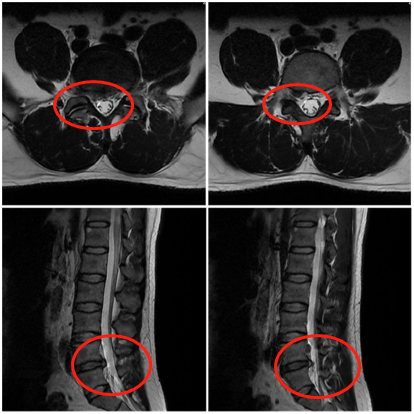

卓玛的腰椎核磁上可以清晰地看到l4/5椎间盘突出,突出为旁中央型;纤维

图片尺寸474x455